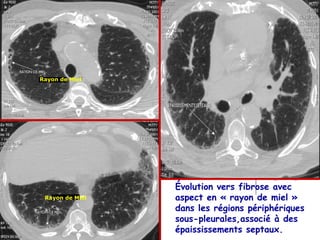

Série B – Cas n°1

Rayon de Miel

Évolution vers fibrose avec

Rayon de Miel   aspect en « rayon de miel »

dans les régions périphériques

sous-pleurales,associé à des

épaississements septaux.